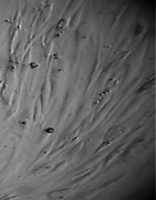

Монослой оставался целостностным и равномерным на всей поверхности чашки Петри, клетки вблизи образца сохраняли характерное для культуры фибробластов взаимное расположение и направление роста (рис. 39).

Морфология их также соответствовала сроку роста: клетки веретеновидной формы с гомогенной цитоплазмой и центрально расположенным пузырьковидным ядром неплотно прилежали друг к другу и анастомозировали своими отростками.

В последующие сроки мы также не наблюдали каких-либо морфологических признаков воздействия имплантата на культуру фибробластов.

Клетки формировали равномерный монослой, плотность которого соответствовала сроку роста культуры после пассирования и не зависела от расстояния до образца (таб. 17).